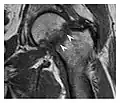

Proximal femoral fractures usually occur in osteoporotic patients, and their signs include subtle neck angulation, trabecular angulation, and subcapital impaction line. A frog-leg lateral view may be helpful if the greater trochanter is short enough. However, positioning can be difficult because of hip pain. In patients with strong suspicion of proximal femoral fracture and negative radiographs, MRI limited to coronal T1 W images and scintigraphy can be highly valuable (Figures 13 and 14). Such an option, with limited examination time, is cost-effective and allows reliable exclusion or confirmation of the diagnosis, preventing an unnecessary stay at the hospital or delayed treatment. Moreover, MRI helps to detect soft tissue abnormalities which are more frequently seen in femoral, acetabular, and pubic injuries than sacral lesions. Concomitant fractures are also frequently seen in typical pelvic sites.[1]

Figure 13: Partial osseous avulsion of the gluteal muscles at the greater trochanter in a 59-year-old man who presented with the right hip pain without a history of trauma. Lauenstein view and anteroposterior and radiographs (not shown) did not show an obvious fracture line or disruption of bony contours in the acetabulum or the right femoral neck. (a) Coronal T1-weighted MRI displays an incomplete fracture line extending partially from the greater trochanter (arrow). (b) Coronal short tau inversion recovery MRI shows heterogeneous hyperintensity in the same region (arrow) as well as hyperintensity within the gluteus medius and minimus muscles (arrowheads) consistent with tissue edema and hematoma.[1]